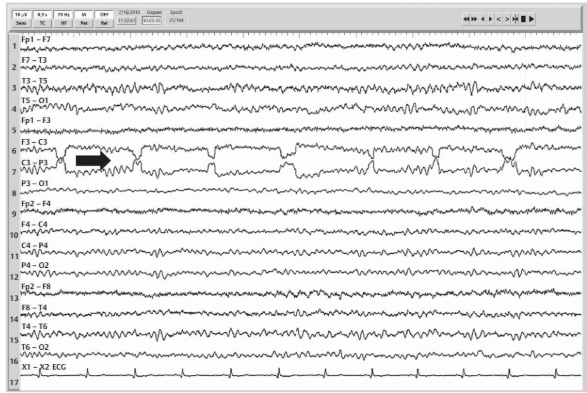

WHAT IS SHOWN?

Single electrode artifact at T5.

Potentials that are confined to a single electrode derivation are suspicious for a single (or common electrode in average/linked montages) electrode artifact